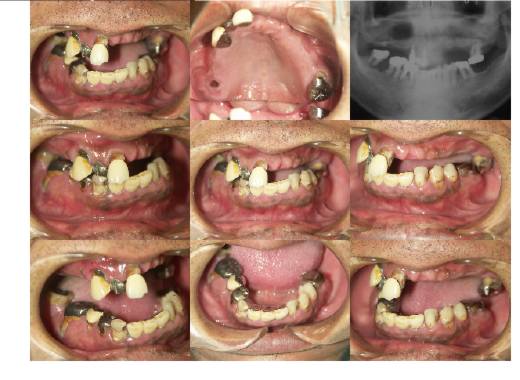

インプラントの症例集

当院で治療された方々の新しい症例を

ご紹介します。

症例1

男性